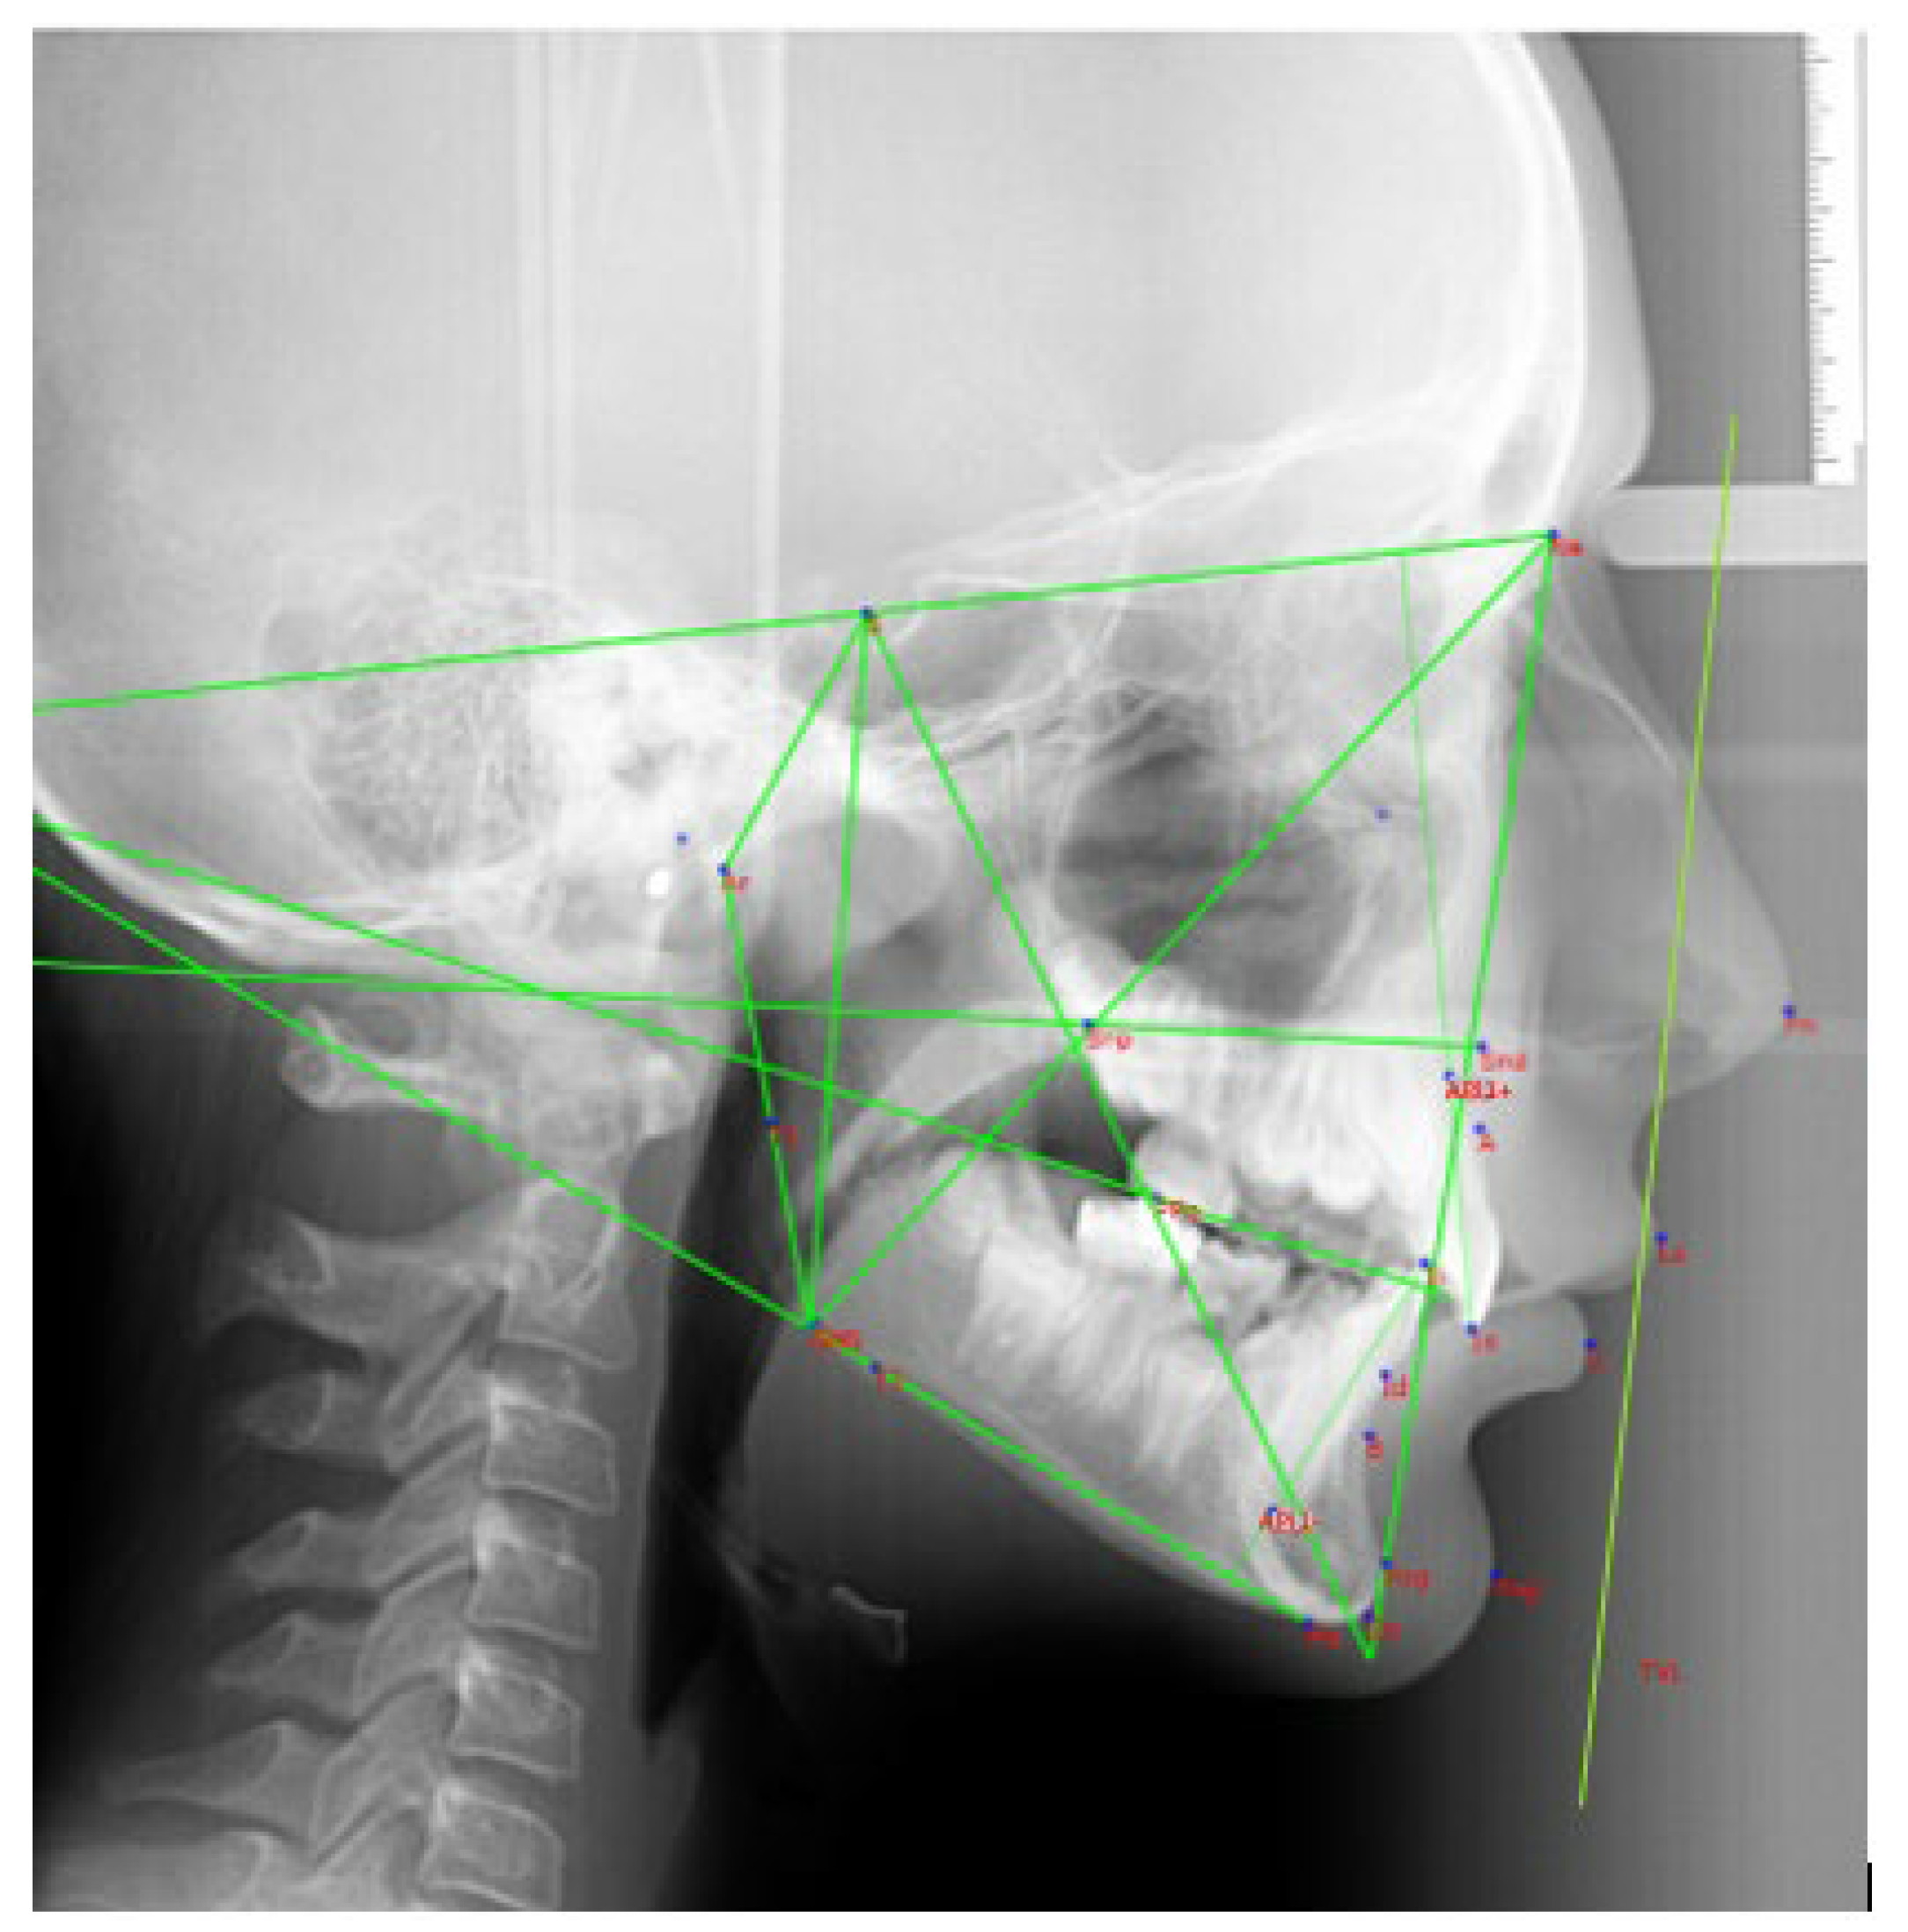

2.4. Cephalometric Analysis

| Dental measurements | |

| 1+SN | Basal incisor angle between the line joining S-N and the straight line passing between the incisal edge and API+ (Apical Point upper Incisor) |

| IMPA | Incisor angle between the line passing through the lower incisor margin and API- (Apical Point lower Incisor) and the Go-Me line |

| 1+TVL | Linear distance between the most vestibular point of 1+ and the TVL |

| Aesthetic measurements | |

| SupportLab-TVL | Linear value of the distance between the lip support point and the True Vertical Line |

| UL-TVL | Linear value of the distance between the most protruding point of the upper lip and the True Vertical Line |

| LL-TVL | Linear value of the distance between the most protruding point of the lower lip and the True Vertical Line |

| B’-TVL | Linear value of the distance between the most recessed point of the chin and the True Vertical Line |

| POG’-TVL | Linear value of the distance between the most protruding point of the chin and the True Vertical Line |